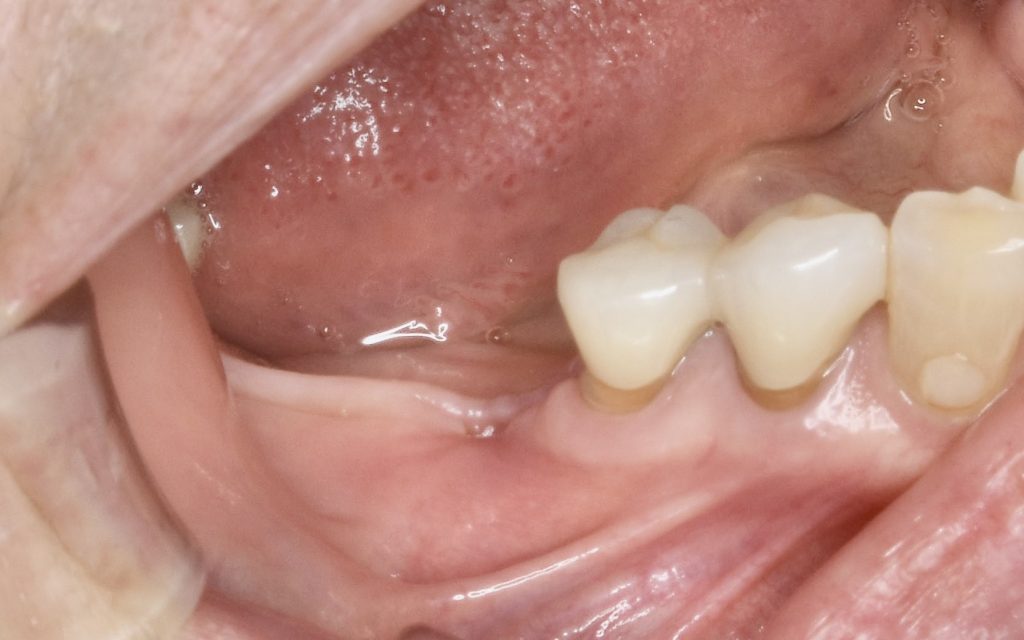

下記の症例はインプラントだけ埋入すれば良いわけではありません。

周囲環境を整え長期的に安定し、長持ちさせるインプラントを目指す必要があります。

その為に歯肉を移植しインプラント周囲に強い抵抗力を持つ歯肉を作る事が大切です。

遊離歯肉移植術にかかる費用 約121000円(税込)